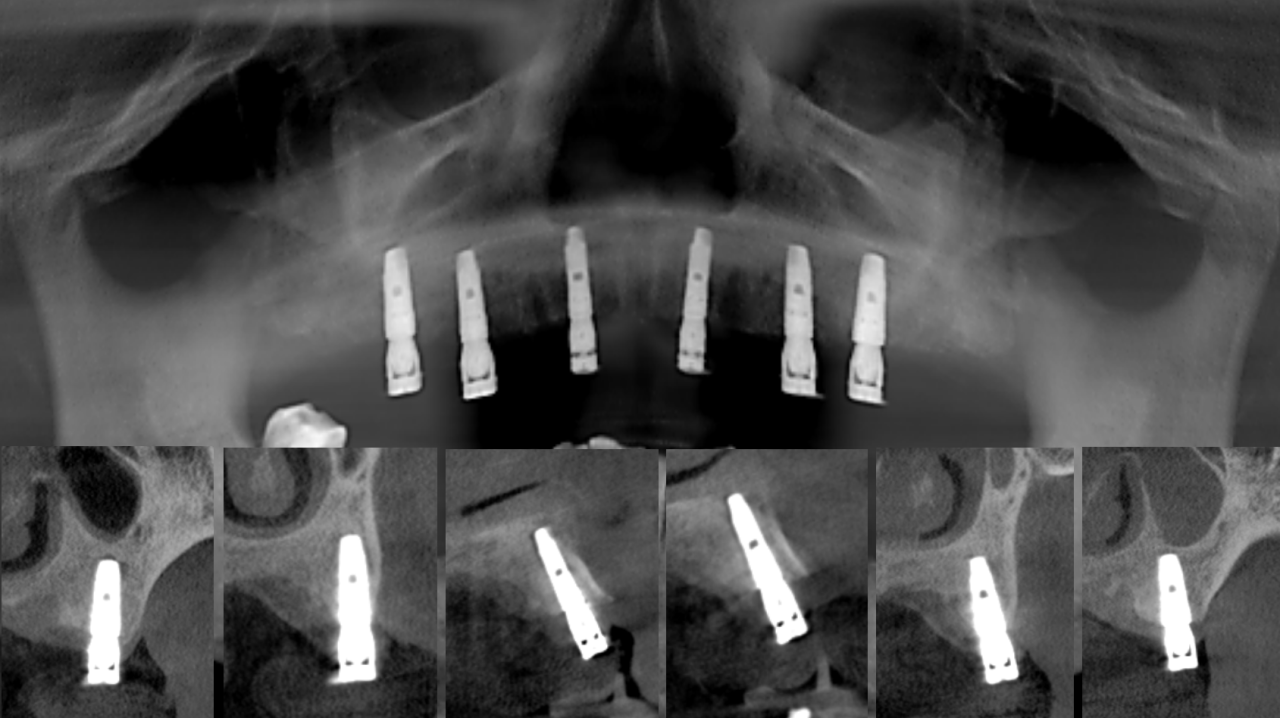

永久修复3年随访:

上下颌边缘骨稳定,零骨吸收

通过修复后口内照观察到,美学效果良好,无基台种植体配合性能相关的周围炎。通过医学影像观察到,修复三年后种植体周围无骨吸收,患者非常满意。